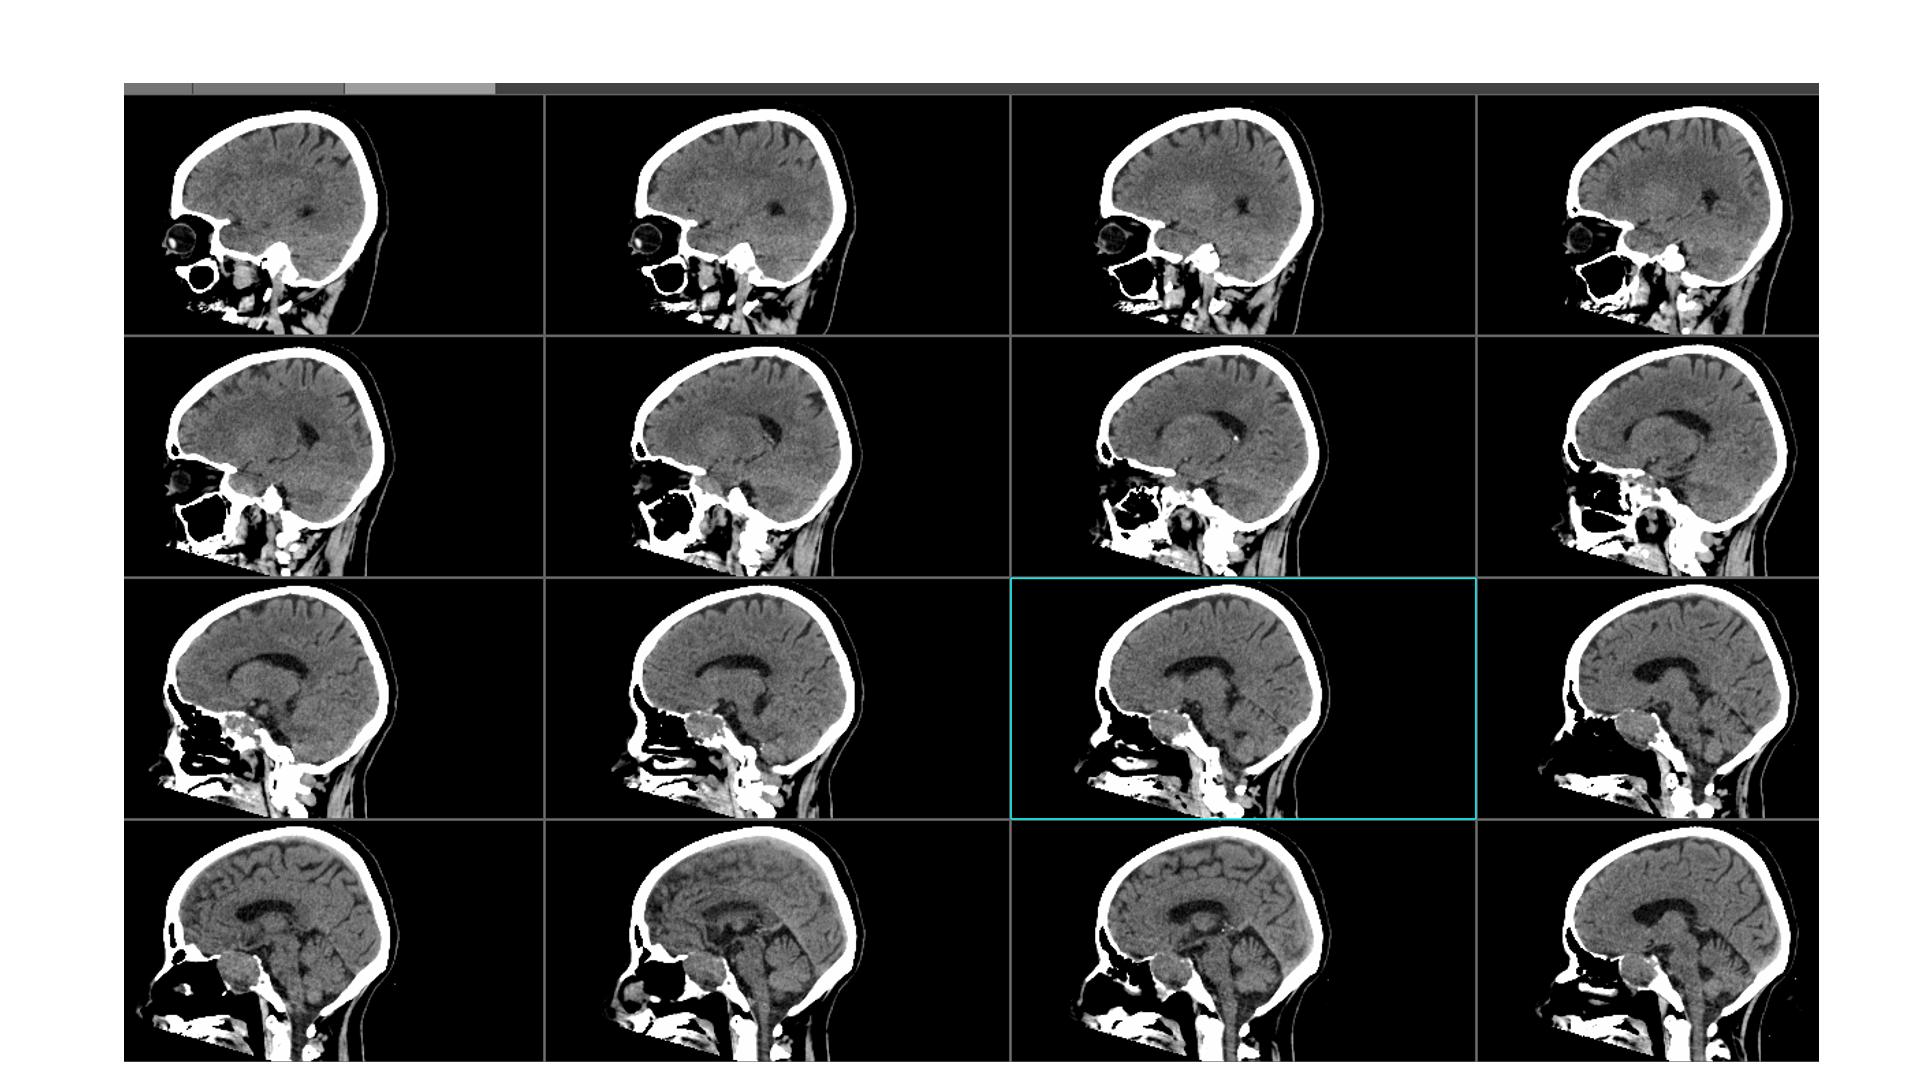

鞍区占位,蝶鞍扩大明显,侵袭海绵窦。